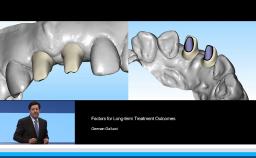

This presentation begins with a discussion of strategic extraction: whether teeth should be extracted as a first choice or kept as long as they function. An overview of estimated numbers of placed and failed implants internationally is given, and differences between the treatment strategies of prosthodontists, periodontists, general practitioners, and surgeons are presented. The definition, prevalence, and risk factors of peri-implantitis and related problems are emphasized. Assessment and diagnosis of peri-implantitis, the importance of radiographic assessment, and evaluation of progressive bone loss are described. The main part of the presentation concentrates on viable treatment options such as antibacterial therapy and ultrasonic debridement, highlighting that prevention is the best treatment.